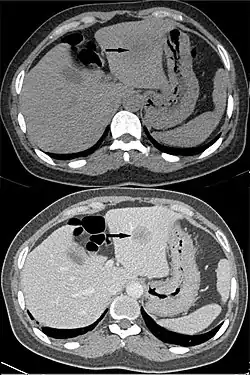

Washout

"Washout" is where tissue loads radiocontrast during arterial phase, but then returns to a rather hypodense state in venous or later phases. This is a property of for example hepatocellular carcinoma as compared to the rest of the liver parenchyma.[3]